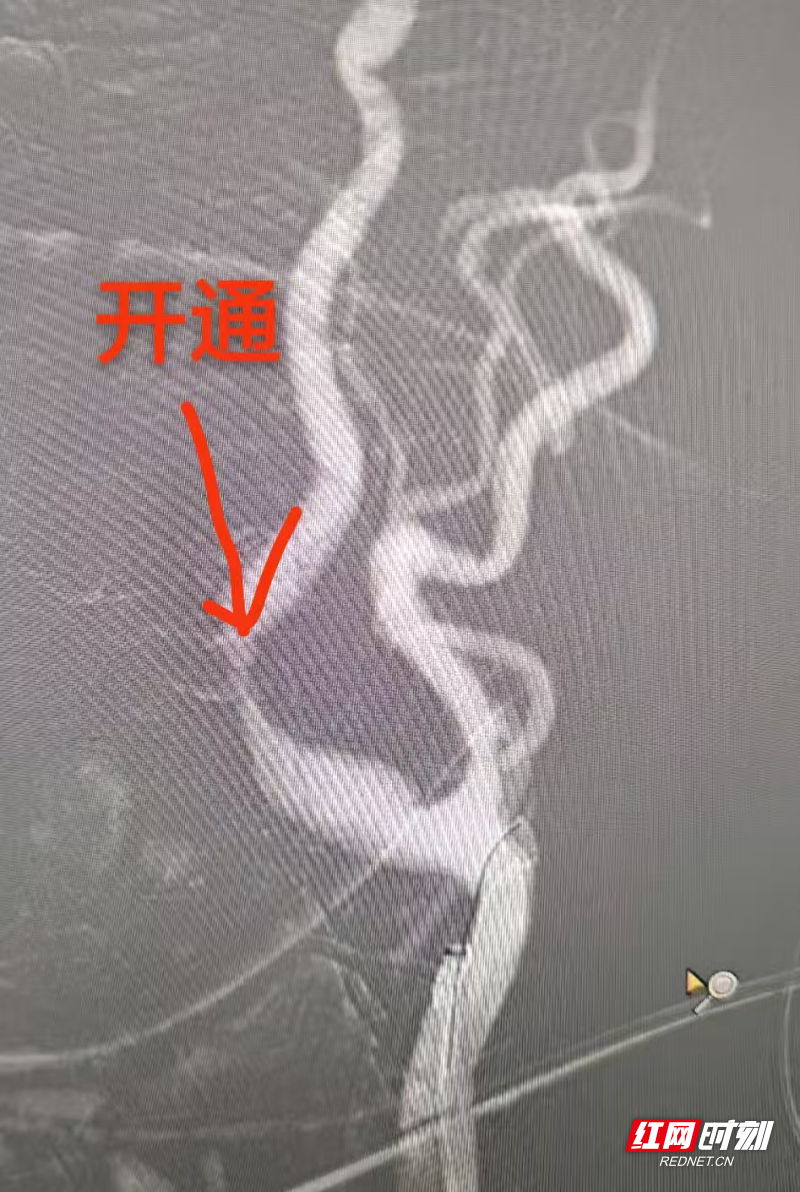

授权即行动!卒中中心绿色通道全程开启,患者第一时间接受静脉溶栓。与此同时,主治医师迅速开展急诊血管内介入手术。造影证实“左侧颈内动脉急性闭塞”,团队立即行颈动脉再通,利用微导丝、球囊精准开通血管。术后影像显示:血流恢复通畅!